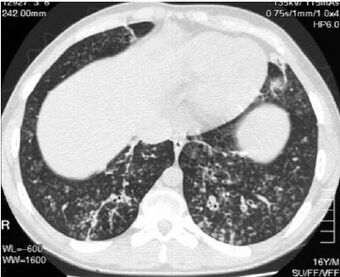

High-resolution computed tomography images of the lower chest in a 16-year-old boy with diffuse panbronchiolitis | |

The diagnosis of DPB requires analysis of the lungs and bronchiolar tissues, which can require a lung biopsy, or the more preferred high resolution computed tomography (HRCT) scan of the lungs.[7] The diagnostic criteria include severe inflammation in all layers of the respiratory bronchioles and lung tissue lesions that appear as nodules within the terminal and respiratory bronchioles in both lungs.[4] The nodules in DPB appear as opaque lumps when viewed on X-rays of the lung, and can cause airway obstruction, which is evaluated by a pulmonary function test, or PFT.[6] Lung X-rays can also reveal dilation of the bronchiolar passages, another sign of DPB. HRCT scans often show blockages of some bronchiolar passages with mucus, which is referred to as the "tree-in-bud" pattern.[7] Hypoxemia, another sign of breathing difficulty, is revealed by measuring the oxygen and carbon dioxide content of the blood, using a blood test called arterial blood gas. Other findings observed with DPB include the proliferation of lymphocytes (white blood cells that fight infection), neutrophils, and foamy histiocytes (tissue macrophages) in the lung lining. Bacteria such as H. influenzae and P. aeruginosa are also detectable, with the latter becoming more prominent as the disease progresses.[4][5] The white blood, bacterial and other cellular content of the blood can be measured by taking a complete blood count (CBC). Elevated levels of IgG and IgA (classes of immunoglobulins) may be seen, as well as the presence of rheumatoid factor (an indicator of autoimmunity). Hemagglutination, a clumping of red blood cells in response to the presence of antibodies in the blood, may also occur. Neutrophils, beta-defensins, leukotrienes, and chemokines can also be detected in bronchoalveolar lavage fluid injected then removed from the bronchiolar airways of individuals with DPB, for evaluation.[4][9]